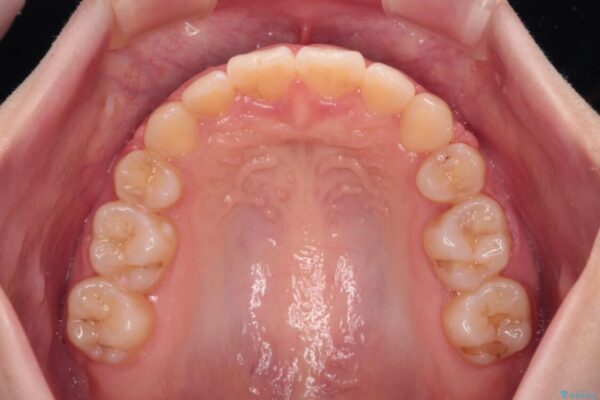

治療後

• 【モニター】口が閉じられない ワイヤー装置での抜歯矯正 治療後画像

治療後について

舌の突出癖があり、前歯の移動量も多くなるため、治療期間は長くなると予想されましたが、13ヶ月という予定の半分程度の期間で終えることができました。